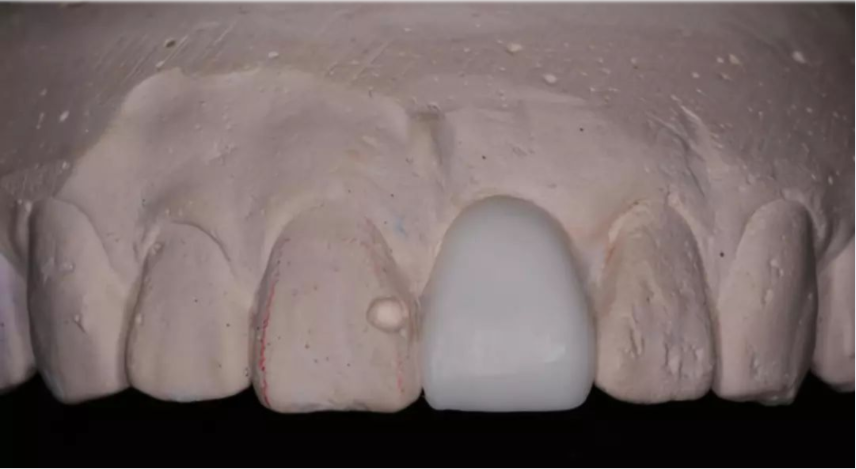

術(shù)前制取參考模型,排美學蠟型,實現(xiàn)以美學修復(fù)為導(dǎo)向的種植

使用U型管作為局部托盤,在石膏模型上,應(yīng)用聚醚硅橡膠進行印模

待硅橡膠凝固后,在印模中21缺牙區(qū)灌注阻射性材料(磷酸鋅或硫酸鋇/自凝牙托粉)

待阻射性材料凝固后,修整其邊緣及組織面